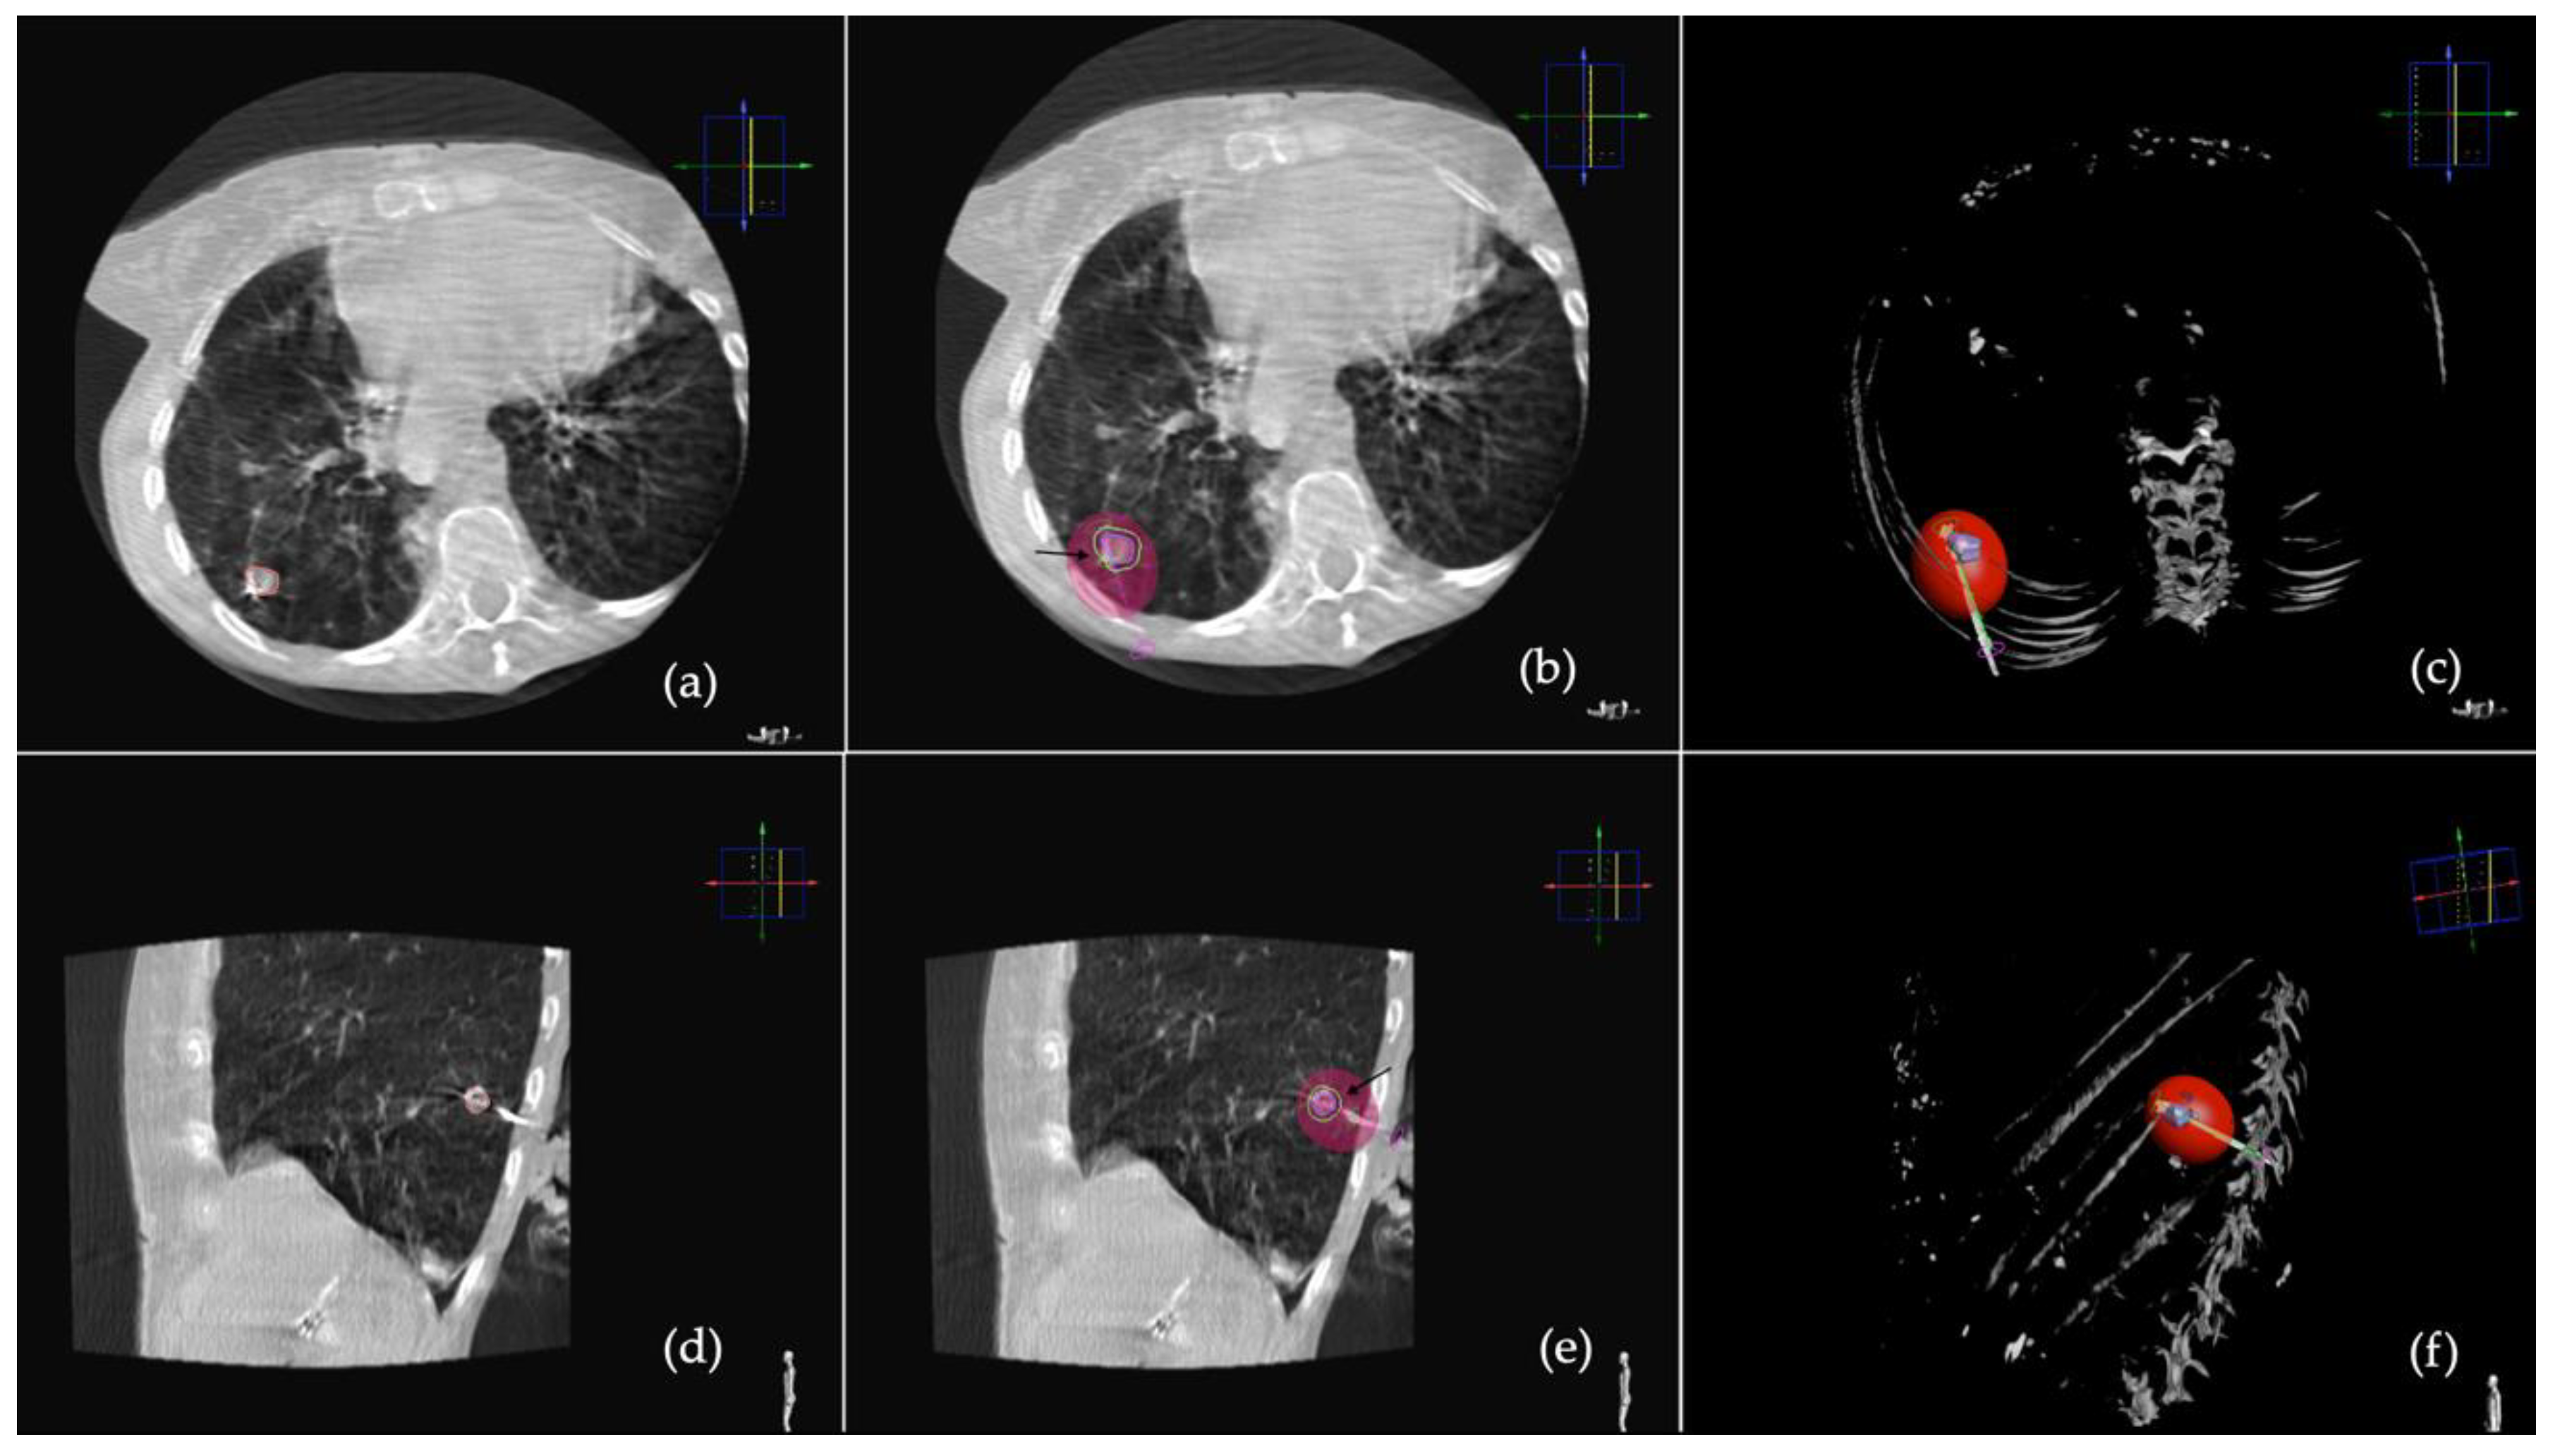

2.2. Procedure